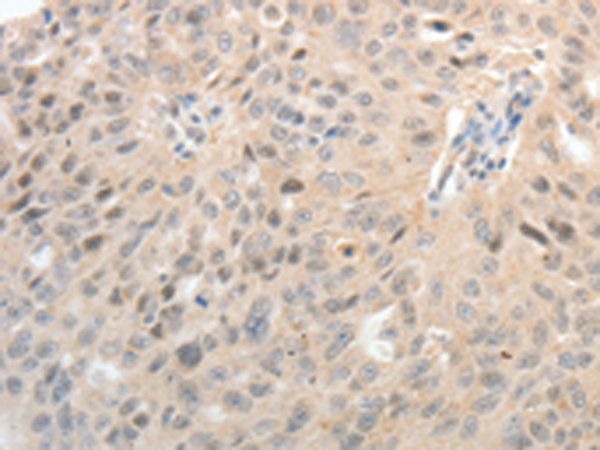

分类: 科研抗体货号: P10708别名: ASH1; HASH1; MASH1; bHLHa46应用: IHC反应种属: Human, Mouse, Rat